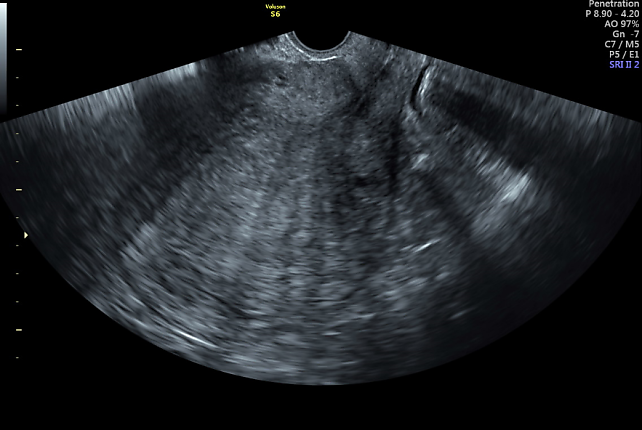

2

Ultrasound image showing an enlarged globular uterus, with diffuse fan-shaped shadowing and an irregular junctional zone. This is indicative of severe diffuse adenomyosis, Type 1–3.